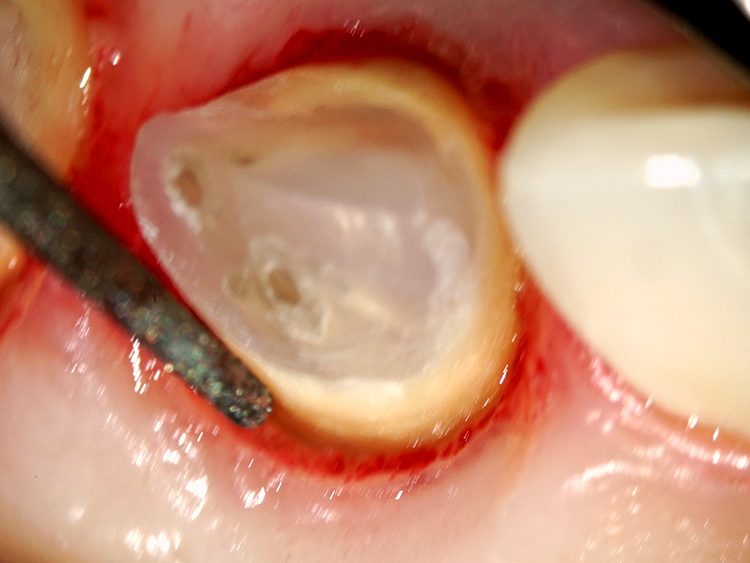

これ以上歯を傷めない低侵襲な歯質除去と形成

このような残存歯質が少ない症例では、これ以上のダメージを与えないよう細心の注意を払った治療が不可欠です。そのため、歯質を削る際には、通常用いられる高速回転ドリルではなく、特殊な超音波振動を用いた専用機器を採用します。これにより安全確実で優しく繊細な施術を可能にしています。

最終的なセラミックス冠を装着する前に、仮歯の形態を調整しながら、健全な歯周組織の回復を誘導します。

炎症を起こし赤みを帯びていた歯肉は、徐々にピンク色に引き締まり、厚みが回復してきました。健全に回復した歯肉からは、細菌侵入に抵抗する白血球を豊富に含む滲出液が分泌され、これにより治療後の虫歯や歯周病の予防効果が高まります。